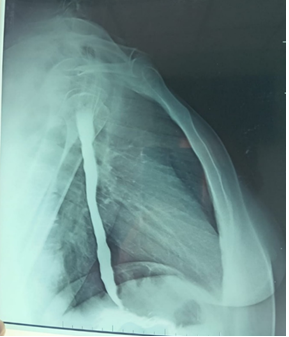

Esophagogastroduodenal series showed a dilated esophagus with a well-defined bird’s beak appearance at the esophagogastric junction (Figure 1).

Esophageal achalasia.